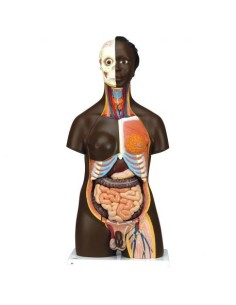

Scopri il Mondo dell’Anatomia con Modelli anatomici di Precisione

Modelli Anatomici Dettagliati per Ogni Necessità

Dal cranio in 22 parti con incastri magnetici ai modelli di colonna vertebrale, da quelli di articolazioni a quelli di cuore, ogni pezzo della nostra collezione è progettato per un’immersione totale nello studio dell’anatomia umana. I nostri modelli, realizzati tramite scansioni di ossa vere, garantiscono un’esperienza tattile autentica e una fedeltà di peso quasi identica agli originali.

Strumenti Didattici Innovativi per l’Educazione e la Pratica Medica

Essenziali per studenti e professionisti, i nostri modelli anatomici sono strumenti didattici che permettono di osservare le strutture anatomiche con precisione, eliminando la necessità di dissezioni o studi invasivi. Sono inoltre utili per spiegare ai pazienti le patologie, rendendo la comunicazione più efficace e risparmiando tempo prezioso.